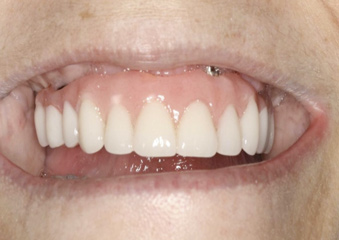

Fig 13. An All-on-4 approach was used to treat both arches with interim immediate and eventual definitive restorations.

Figure 13

Fig 14. Final restorations used for 6-1/2 additional years.

Figure 14

This is an unfortunate mindset in that current advances in protocol and technology can result in significant advantages in addressing some or most of these concerns. The patient shown in Figure 12 may serve to illustrate this point. She had a destroyed maxillary dentition, a less-compromised but highly unesthetic mandibular component, and a single goal: to be able to "smile at my grandchildren again." In consultation with her and her family, it was decided that a double-arch fixed implant approach would most realistically address her esthetic goals and provide her with the desired prosthetic result. She was 102 years old at the time of initial consultation. Using a staged operating-room approach, provisional restorations were initially delivered, followed by subsequent definitive hybrid final restorations. She was able to use these comfortably for the next 6-½ years (Figure 13 and Figure 14).